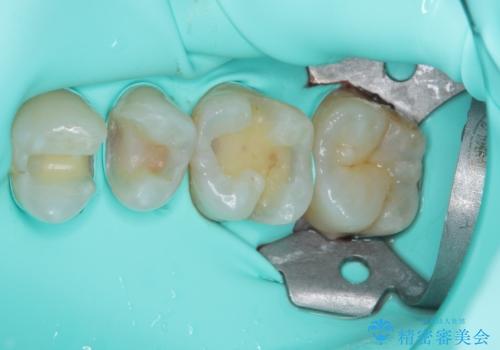

インレーを装着するときは、唾液や血液による接着力の低下を避けるためにラバーダム防湿を行いました。

そして次の来院時、セラミックインレーを装着し、噛み合わせなどの調整を行います。